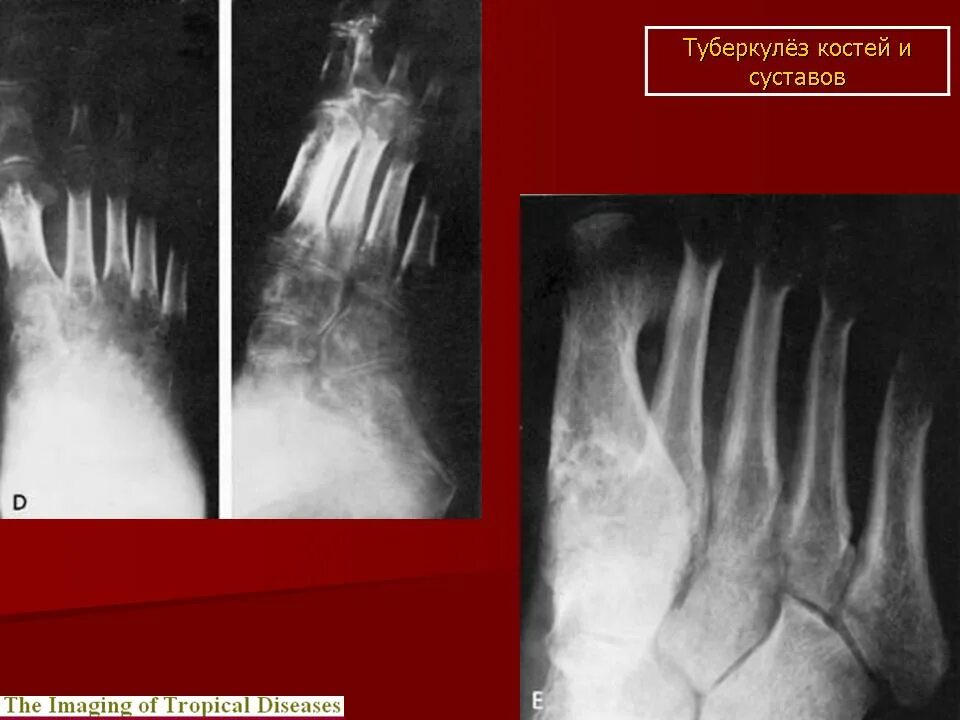

Туберкулез суставов симптомы